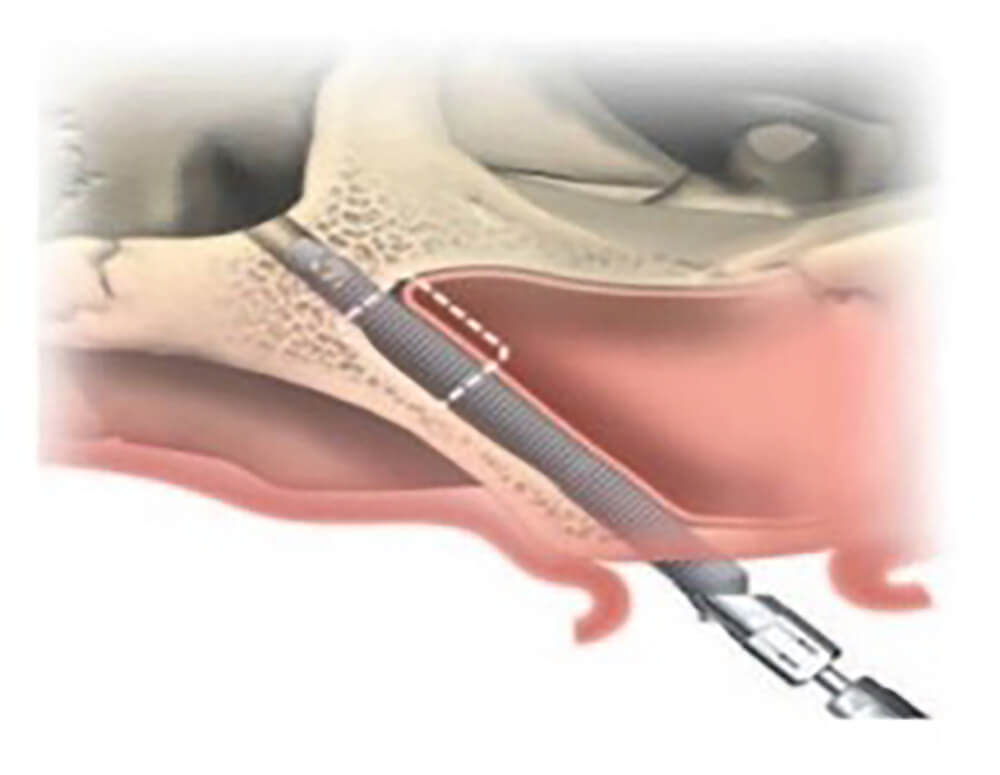

All-on-4 全口重建術式原理是植入 4 顆特殊設計的植體,藉由造橋力學原理,讓力量平均分散支撐整排牙齒。若患者骨質無法達到 All-on-4 全口重建傾斜植體的條件,Zygoma implant 顴骨植體就是最後秘密武器,顴骨是顏面主要支架,骨質密度高且強壯,不易隨著時間流失,足以提供植體良好穩定性,讓骨質不佳的患者也有接受 All-on-4 全口重建治療的機會。

這次All-on-4 全口重建案例盤太太,經醫師評估後即使用 2 根顴骨植體來確保全口重建假牙的穩固。(延伸閱讀:【顴骨植體】骨頭不好無法做All-on-4全口重建? Zygoma implant 顴骨植體有解!)